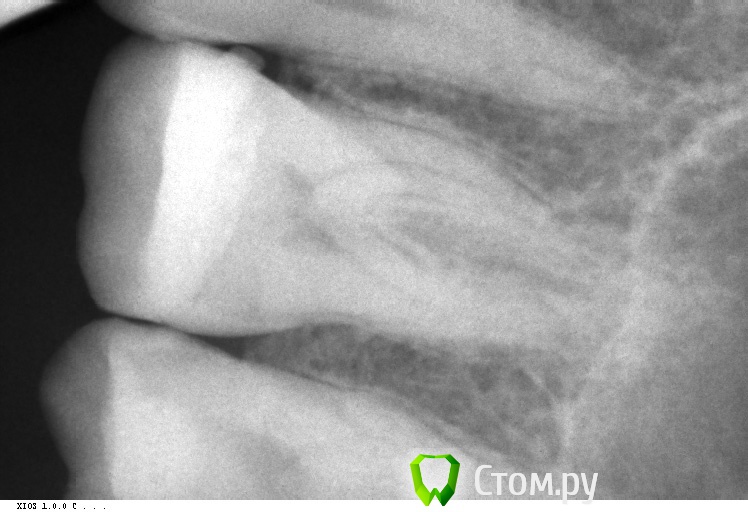

Барсук Опубликовано 12 марта, 2014 Поделиться Опубликовано 12 марта, 2014 (изменено) Добрый день уважаемые специалисты! Такая проблема... немного предыстории. Лет 15 назад верхнюю 6-ку заплобировали.В том году случился рецидив, заделали, получилась довольно большая пломба.Недавно в районе этого зуба стало иногда ныть, и как бы зуд такой, особенно после еды. Помогала чистка. И вот во время чистки нитью я обнуражил, что если пошерудить пальцем десну рядом с зубом - то он очень неприятно пахнет какой-то гнилью - тухлятиной, фу-фу-фу.Именно в районе этого зуба.Был у стамотолога, сделали снимки, он никаких паталогий не обнаружил, заметил только на снимке между зубов выступающую пломбу и зашлифовал, вдруг там остатки еды скапливаются. А вскрывать зуб пока смысла нет, тем более если вскрывать то придется уже депульпирвоать и скорее всего вкладку делать. Две недели прошло, все так же воняет десна.Когда промываю ирригатором в определенном месте между зубами есть заметная чувствительность.К слову сказать, ирригатор помогает на минуту. Потом снова если надавить-пошерудить пальцем - тот будет вонять.Но целом на холодное/горячее не реагирует. Есть мысли?Может к пародонтологу надо? Снимки по-моему не очень хорошие, но какие есть. прилагаю: Изменено 12 марта, 2014 пользователем Барсук Ссылка на комментарий

Zlata-doctor Опубликовано 12 марта, 2014 Поделиться Опубликовано 12 марта, 2014 Некорректная пломба медиальной поверхности? (контактный пункт, нависание) Окончательный диагноз-после осмотра и повторного снимка в другой проекции (или нескольких) Пока не вижу оснований для эндодонтического лечения ни по вашему описанию, ни по снимку. Думаю, что нужна хорошая пломба или вкладка (онлей-инлей) Ссылка на комментарий

Zlata-doctor Опубликовано 12 марта, 2014 Поделиться Опубликовано 12 марта, 2014 (изменено) не могу сказать точно, не видя вас. Возможно застревает пища, пародонтит, локальный зубодесневой карман (хотя я на снимке его четко не вижу), могут быть другие причины. Иногда галитоз вызван причинами, не связанными с полостью рта. Там и на дистальной поверхности надо повнимательней посмотреть, возможно кариес под пломбой (нужен четкий снимок в разных проекциях) Изменено 12 марта, 2014 пользователем Zlata-doctor Ссылка на комментарий